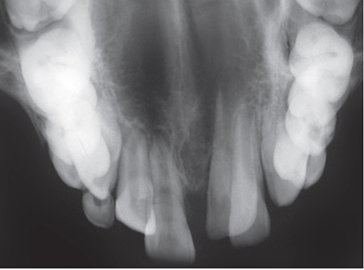

Khám lâm sàng thấy chậm mọc răng so với tuổi mọc dự kiến. Chẳng hạn như tuổi dự kiến mọc răng cửa giữa hàm trên vào khoảng 7-8 tuổi. Khi đến độ tuổi này nếu cả hai răng chưa mọc hoặc đã mọc một răng trong khi răng đối xứng chưa mọc hoặc mọc chậm thì nghi ngờ khả năng có răng thừa ngầm gây cản trở sự mọc răng. Hoặc phát hiện khe răng thưa răng cửa hàm trên hoặc có bất kì sự mọc lệch lạc nào của răng cửa hàm trên đều cũng nên chụp XQ kiểm tra sự hiện diện của răng thừa. Việc chẩn đoán bằng XQ là rất quan trọng. Tại BV Đa khoa Tỉnh Quảng Trị có đầy đủ các phương tiện chẩn đoán như XQ cận chóp, XQ răng toàn cảnh và đặc biệt là phương tiện chụp cắt lớp vi tính chùm tia hình nón (CT Cone Beam) có thể phát hiện răng thừa theo 3 chiều không gian mà các phương tiện khác có thể không phát hiện ra. Minh họa trường hợp cháu trai 8 tuổi sau đây là một ví dụ.

Răng thừa (b) mọc trong vòm miệng khiến cho R22 (a) mọc lệch xoay trục XQ răng toàn cảnh không thấy răng thừa do R21 (a) che khuất,(b) là R22 bị xoay trục